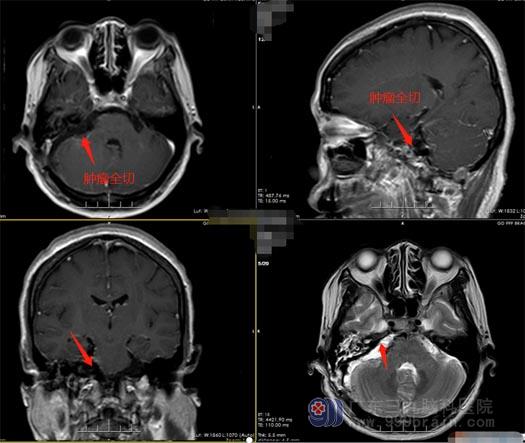

积极完善相关术前准备后,由王国良主任主刀,带领外五科医生团队为华大姐行“右侧桥小脑角区脑膜瘤切除术”,术中显微镜下见肿瘤呈黄白色,血供丰富,全切肿瘤,术中对右侧听神经、面神经、后组颅神经保护完好,手术顺利结束。术后第一天查体:患者神志清醒,饮水无呛咳,无明显面瘫,四肢活动自主,肌力及肌张力未见异常,未出现后组颅神经障碍。术后MR示:原有病灶全切,颅内未见明显出血及梗死。

▲术后